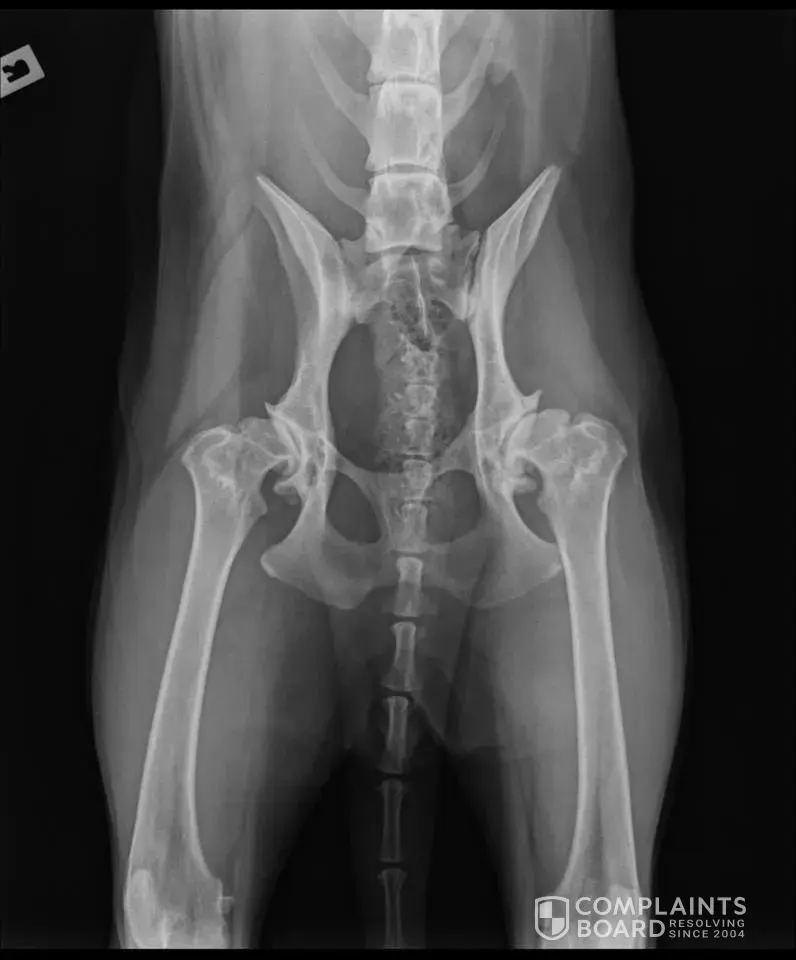

Gipfel German Shepherd Dogs in Milawa - breeder clearly does not hip score his breeding dogs

Sadie is a pedigree dog that came from Gipfel GSDs in Milawa. Her name is Gipfel Royal Fantasy - we prefer to call her Sadie. I rang the breeder to ask if he gets his dogs hipscored etc before breeding and of course he went straight on the defense. I told him we were up for around $18, 000 to fix the serious congenital problem his breeding dogs have (which...

View 0 more photos

Read full complaint and 4 comments